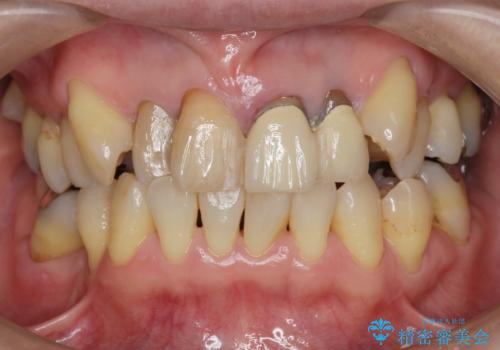

- 前歯のぐらつき、見た目の改善を希望され来院されました。

ぐらつきのある歯は、破折が認められ、その他前歯も不十分な根管治療や不適合なクラウン、レジン修復により審美障害が起きています。

問題を一つづつ丁寧に解決し、前歯の審美性の改善を計画します。